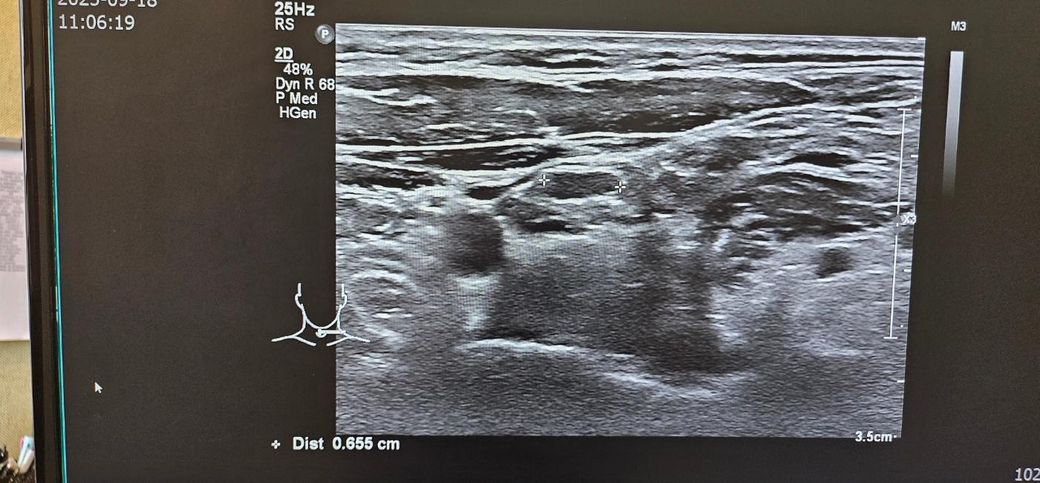

경부 초음파찍었는데 초음파 사진좀 봐주세요.. .

목통증이 있어서 초음파를 했는데

여러개가 부어있다고 하셨습니다

• 4번 째 사진

초음파 소견으로는 림프절들이 보이며 부어 있다 정도로 보입니다. 이외에 특별하나 소견이 따로 있거나 해 보이지 않습니다. 약물 치료를 하여도 회복이 되지 않다면 추가적으로 약물 복용을 해주며 경과를 지켜보거나 보다 정밀 검사를 통해서 다른 문제는 없는지 감별해보는 방향이 있겠습니다. 이비인후과적으로 재차 상담을 받아보시는 것을 권고드립니다.